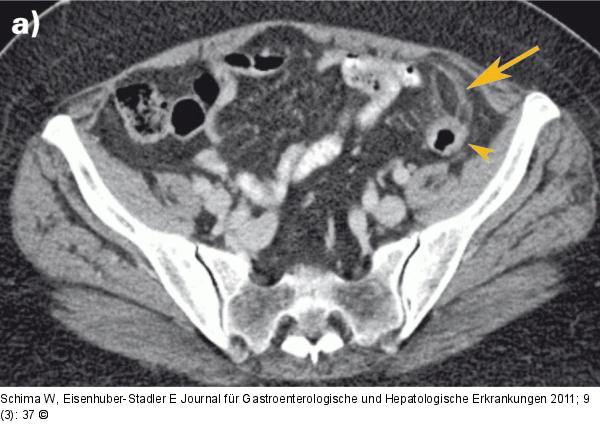

Abbildung 1a: MDCT Die axiale kontrastmittelverstärkte Multidetektor-CT (MDCT) zeigt eine fetthältige Appendix epiploica (Pfeil) mit einem entzündlichen Halo und einem zentralen "Punkt", der dem thrombosierten nutritiven Gefäß entspricht. Pfeilspitze: Colon sigmoideum. |

Die axiale kontrastmittelverstärkte Multidetektor-CT (MDCT) zeigt eine fetthältige Appendix epiploica (Pfeil) mit einem entzündlichen Halo und einem zentralen "Punkt", der dem thrombosierten nutritiven Gefäß entspricht. Pfeilspitze: Colon sigmoideum. |